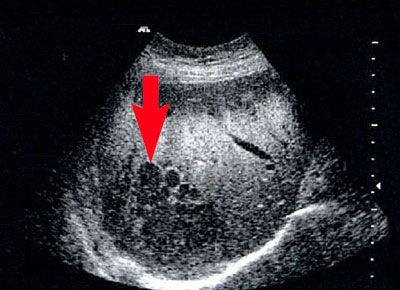

Kontrastmittelsonografie

Kontrastmittel bei Ultraschalluntersuchungen helfen, krankhafte Veränderungen der Niere, der Leber, der Bauchspeicheldrüse und der Blutgefäße im Ultraschall weiter zu unterscheiden.